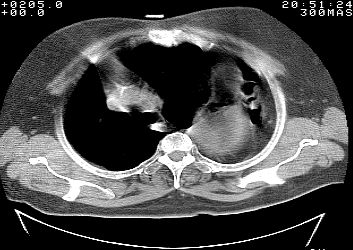

标题: CT10753:女, 64岁 隔疝 [打印本页]

标题: CT10753:女, 64岁 隔疝

女, 64岁 三十年前胸部外伤史, 间断胸闷,

典型左侧膈疝,疝出物为胃和大网膜,纵隔右移

同意左侧膈疝,不过,有过外伤史,左肺有受压征象,同时有胸膜增厚。

典型左侧膈疝,如此严重少见。

左侧隔疝(创伤性?),与外伤关系大。